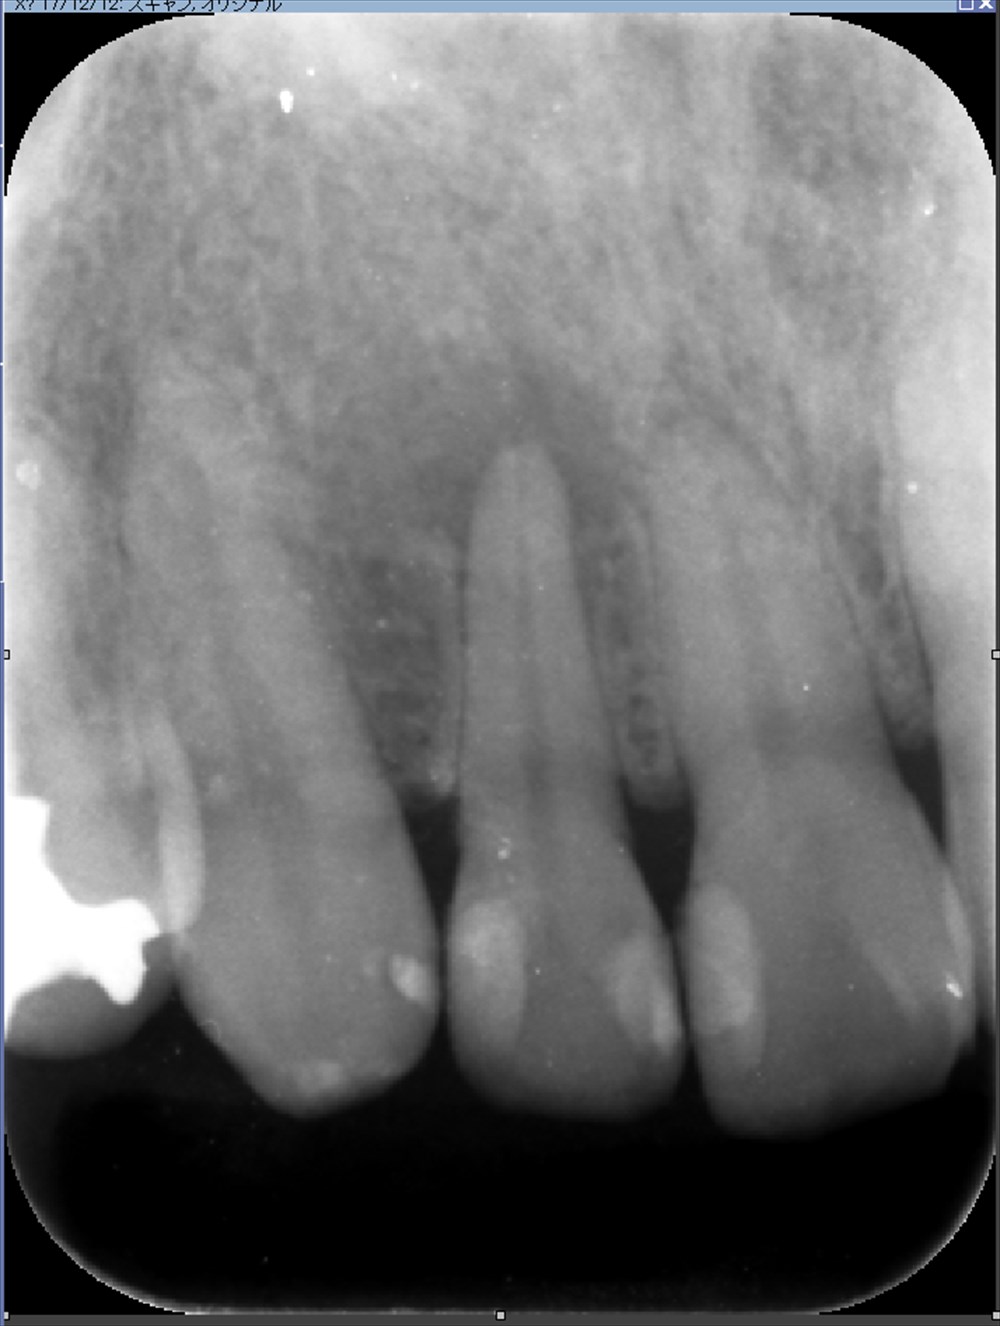

前歯の違和感、はれた感じがする。右上2何かあるぞ。

歯科ドックで精密検査 骨に穴があいている!!!

詳しく原因を調べます。

根尖性周囲炎でした。

ここまで骨がないとは。精密検査だからわかる事です。